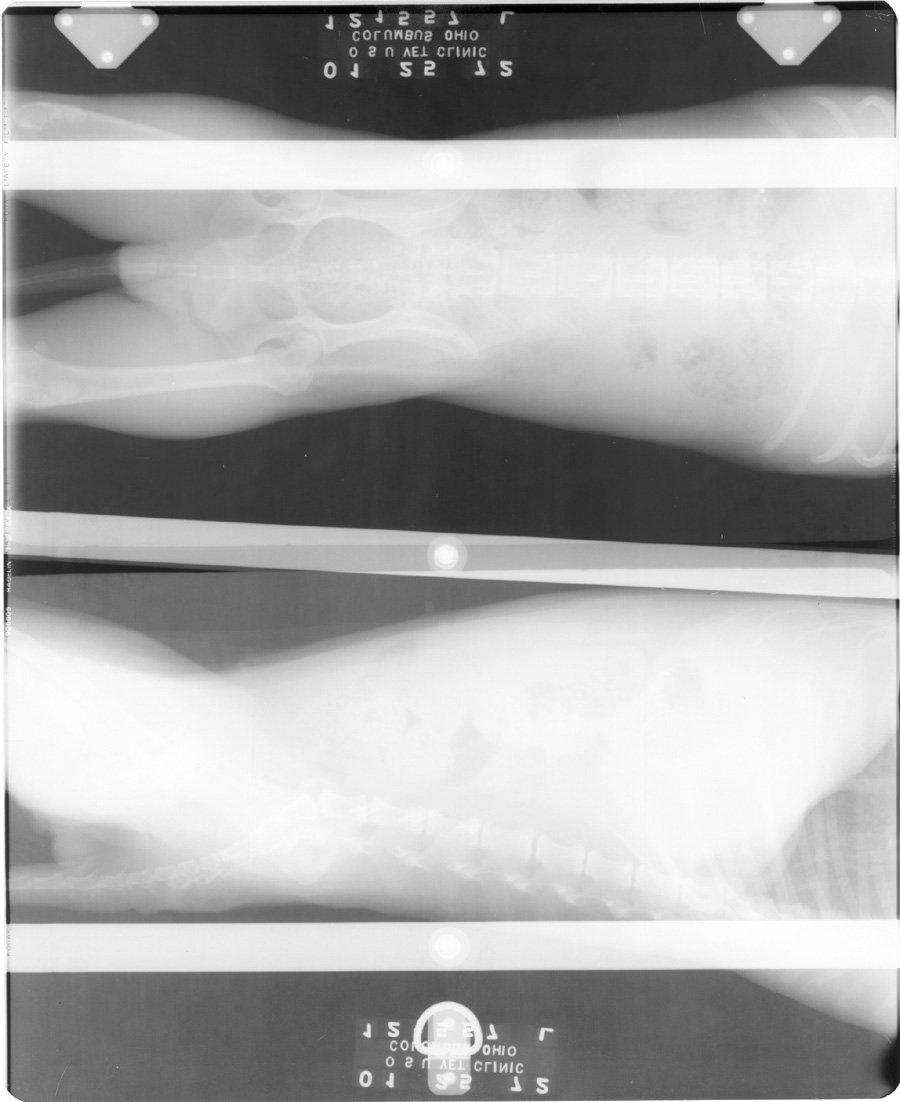

Upside Down Cassettes